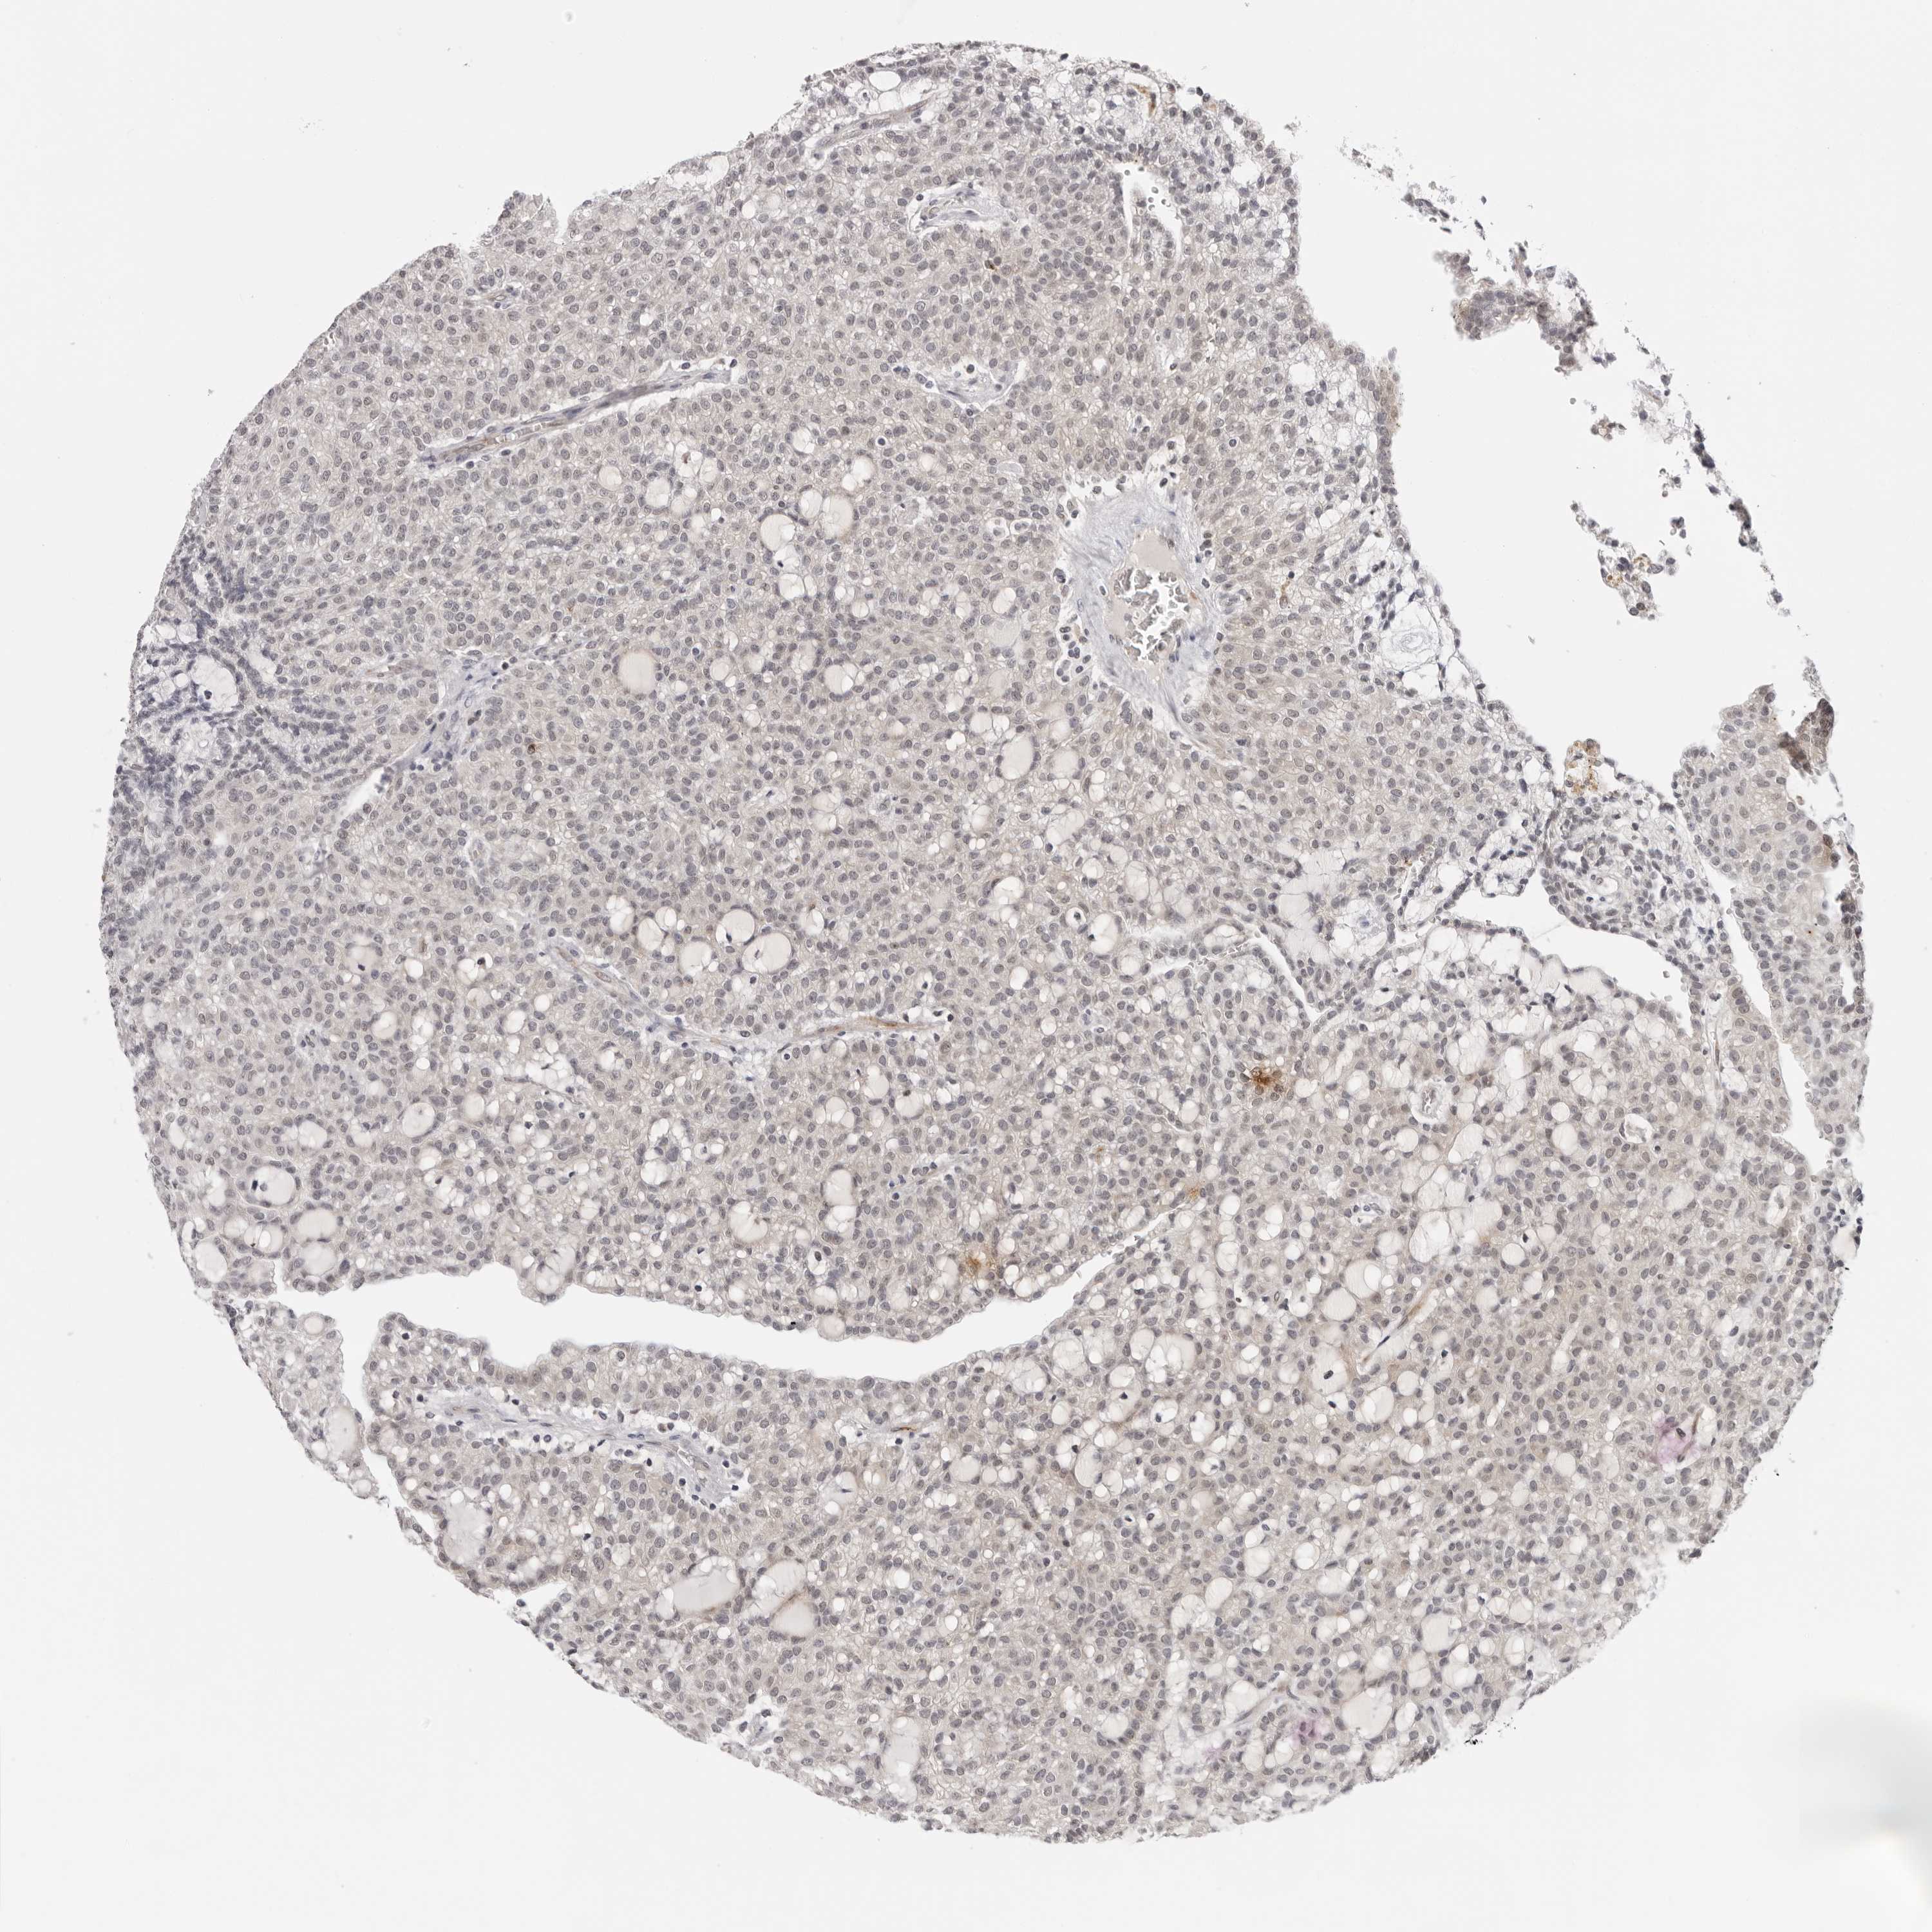

CANCER RENAL CANCER Show tissue menu

KICH TCGA KIRC TCGA KIRC VALIDATION KIRP TCGA PROTEIN RCC CPTAC PROTEIN EXPRESSION